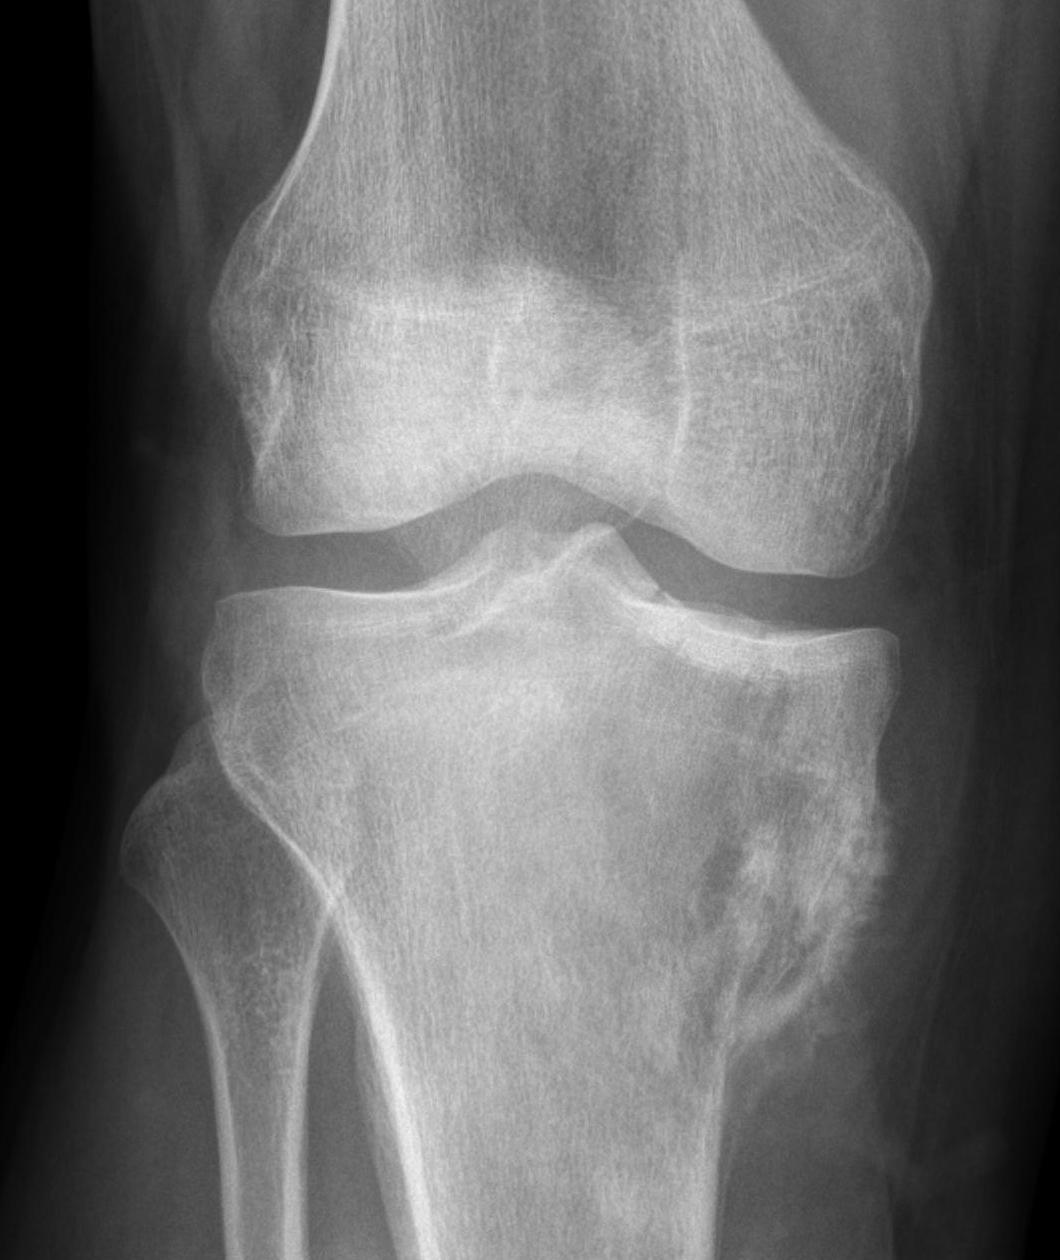

Osteosarcoma of the distal femur

Codman's Triangle

- triangular periosteal new bone formation

- at proximal and distal cortical margins

- reaction to rapid growth

Codman's triangle in osteosarcoma distal femur